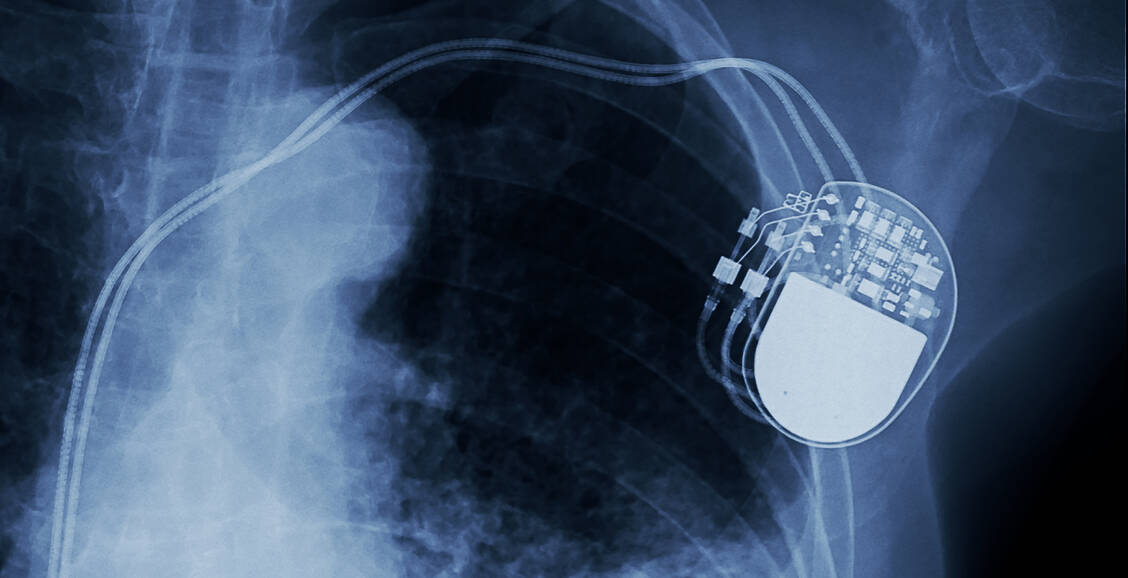

Herzschrittmacher und Insulinpumpen

Hackerangriff möglich

Nicht nur medizinische Großgeräte, auch individuelle Hilfsmittel können prinzipiell von Hackern angegriffen werden. So senden etwa Herzschrittmacher zahlreiche Informationen per Funk oder Mobilfunknetz auf den Bildschirm des Arztes.

Auch Diabetiker profitieren von der drahtlosen Datenübertragung zwischen Blutzuckermessgerät und Insulinpumpe. Für die Patienten ist das oftmals sehr komfortabel, erläutert IT-Sicherheitsexperte Wolfgang Hommel von der Universität der Bundeswehr München. »Aber dass man damit,wenn es ganz blöd läuft, auch um die Ecke gebracht werden kann, ist den meisten nicht bewusst.«

Bislang ist zwar noch kein einziger konkreter Fall bekannt. Doch es gibt viele Beispielhacks mit konkreten Medizinprodukten, bei denen Experten etwa Herzschrittmacher starke Stromimpulse abgeben oder Insulinpumpen hohe Dosen spritzen ließen. Der frühere US-Vizepräsident Dick Cheney war sich dieses Risikos übrigens früh bewusst: Er ließ sich aus Angst vor einem Anschlag schon vor vielen Jahren die Fernsteuerungsfunktion an seinem Herzschrittmacher deaktivieren.